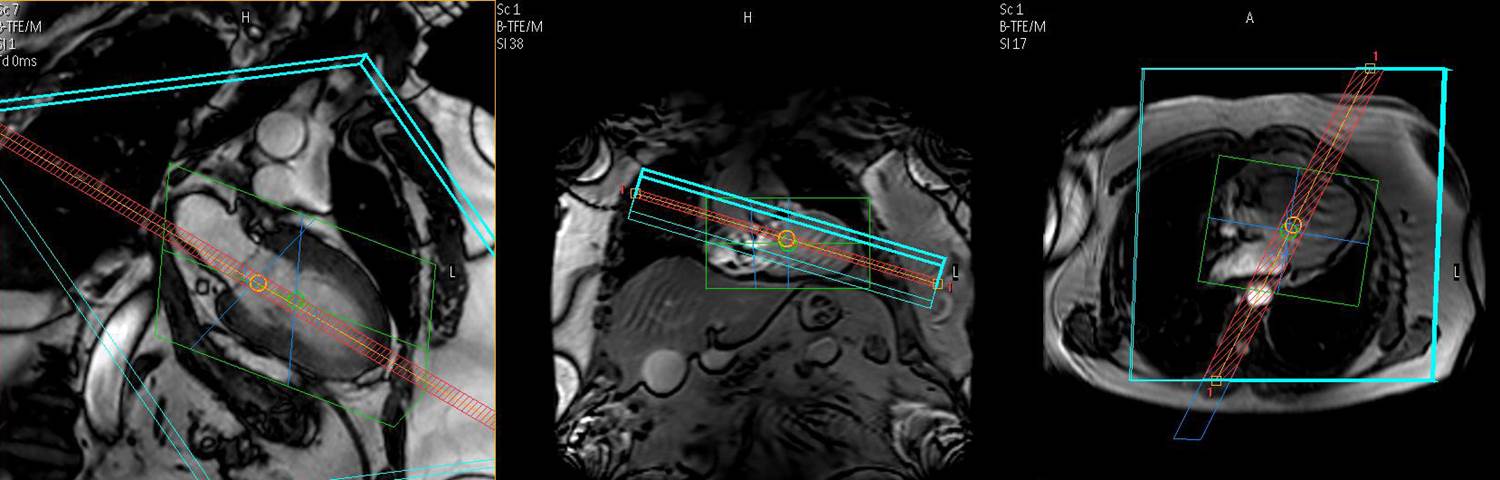

105. Jahnke C, Paetsch I, Nehrke K, Schnackenburg B, Gebker R, Fleck E, Nagel E. Rapid and complete coronary arterial tree visualization with magnetic resonance imaging: feasibility and diagnostic performance. Eur Heart J 2005;26:2313-9.

97. Jahnke C, Paetsch I, Nehrke K, Schnackenburg B, Gebker R, Fleck E, Nagel E. Rapid and complete coronary arterial tree visualization with magnetic resonance imaging: feasibility and diagnostic performance. European heart journal. 2005; 26:2313-2319.